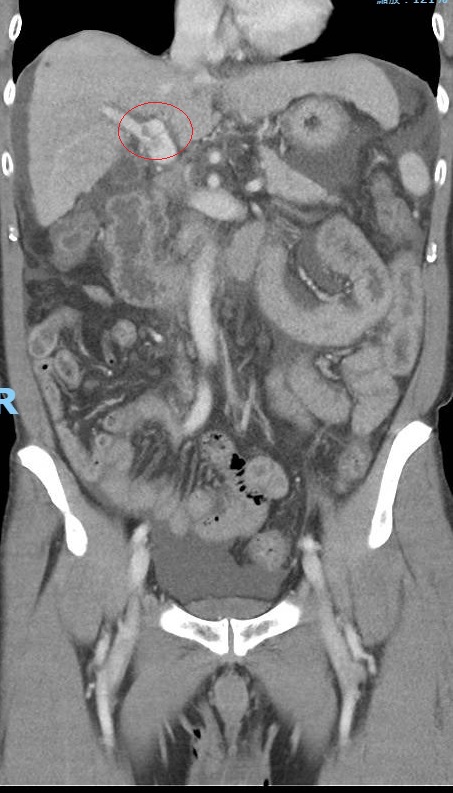

▲B肝沒症狀沒追蹤擴散到肝門靜脈的腫瘤。

(圖/記者陳雅芳翻攝,2022.08.11)

宋時雨指出,肝門靜脈將營養送進肝臟,是供應肝臟養分的主要命脈,肝癌細胞只要侵犯肝門靜脈就屬於第三期,容易引發肝內癌轉移及遠處器官轉移,治療更加困難。